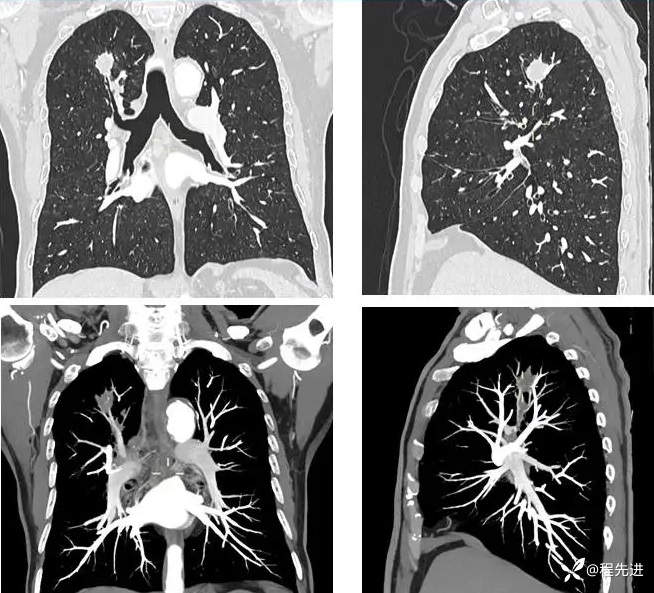

患者性别:男

患者年龄:70岁

简要病史:因“体检发现肺结节10余天”入院,患者平时无明显咳嗽、咳痰,胸闷胸痛咯血、呼吸困难

既往史:吸烟40年,平均每天30支;戒烟10年。高血压、糖尿病。

指脉氧 97% 一般情况可,其他阴性,实验室检查:NSE:20.56 ng/ml↑